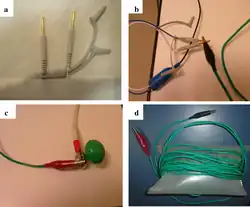

Configuração para fazer um ECG do dispositivo

Configuração para fazer um ECG do dispositivo -